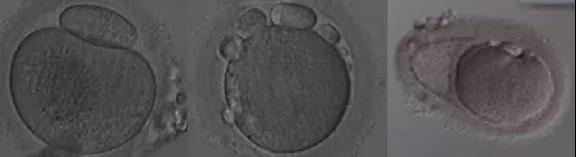

二、異常卵子的形態

在促排卵周期,一批獲卵中總會有少數幾個形態異常的卵子,漂亮的卵子千篇一律,異常的卵子各有各的異常。我們根據異常的類型分為胞漿外形態異常和胞漿內形態異常。目前的觀點認為,卵子的輕微異常并不會影響到胚胎的發育潛力,嚴重的異常卵子才會影響胚胎的發育潛力。當然,這都是形態學的初步評價,成功妊娠并活產才是評價一個卵子質量的金標準。

(圖:胞漿內形態異常)

(圖:胞漿外形態異常)